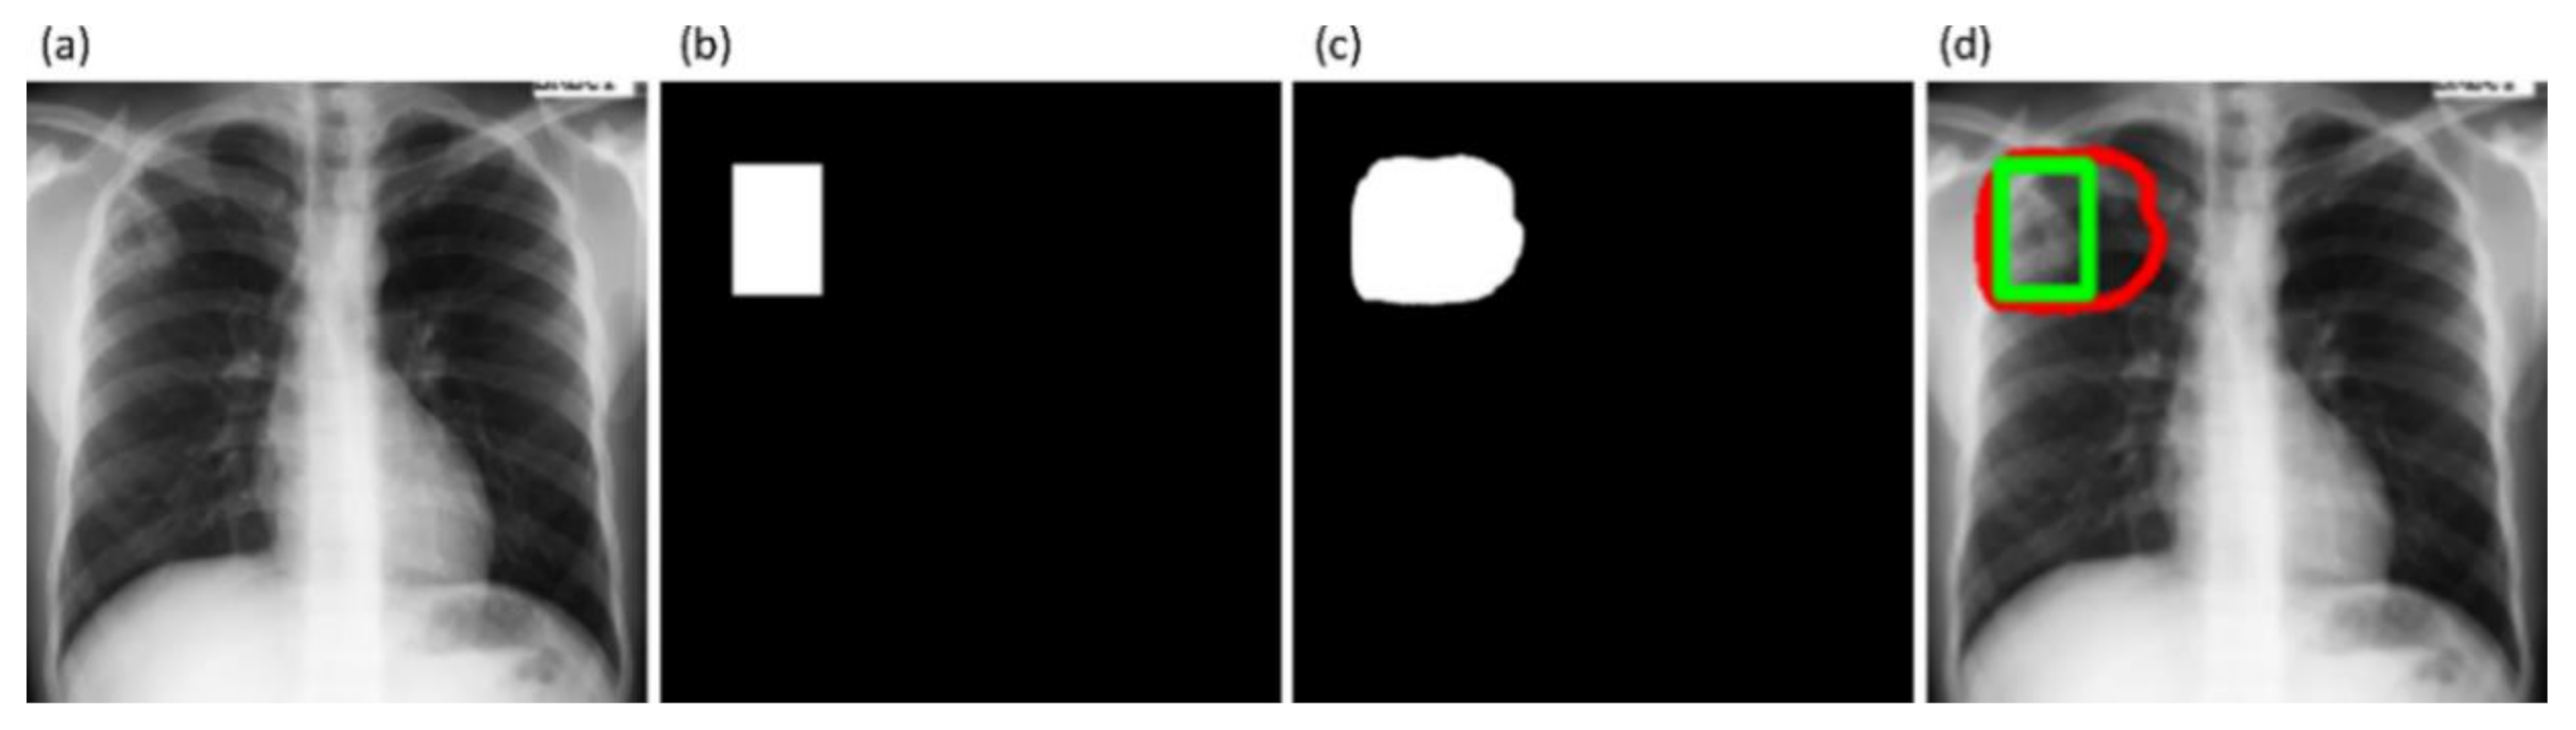

Figure 6 shows instances of TB-consistent

ROI annotations made by the radiologists and the STAPLE-generated consensus

ROI for a sample CXR instance from the Shenzhen TB CXR-Subset-2 and Montgomery TB CXR collections respectively.